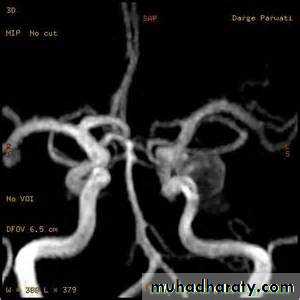

Conventional T1 and T2 sequences are not highly sensitive to hemorrhage in the first few hours, but newer gradient refocused echo sequences appear to be able to detect intracerebral hemorrhage reliably within the first 1-2 hours of onset (MRI studies incorporating gradient echo or susceptibility-weighted sequences may be used as the sole imaging modality for patients with acute stroke, readily identifying intracranial hemorrhage• Vessel imaging

• CT angiography permits screening of large and medium-sized vessels for AVMs, vasculitis, and other arteriopathies.• MR angiography permits screening of large and medium-sized vessels for AVMs, vasculitis, and other arteriopathies.

• Conventional catheter angiography definitively assesses large, medium-sized, and sizable small vessels for AVMs, vasculitis, and other arteriopathies

CT angiography

MRI angiographyCatheter MRI angiography